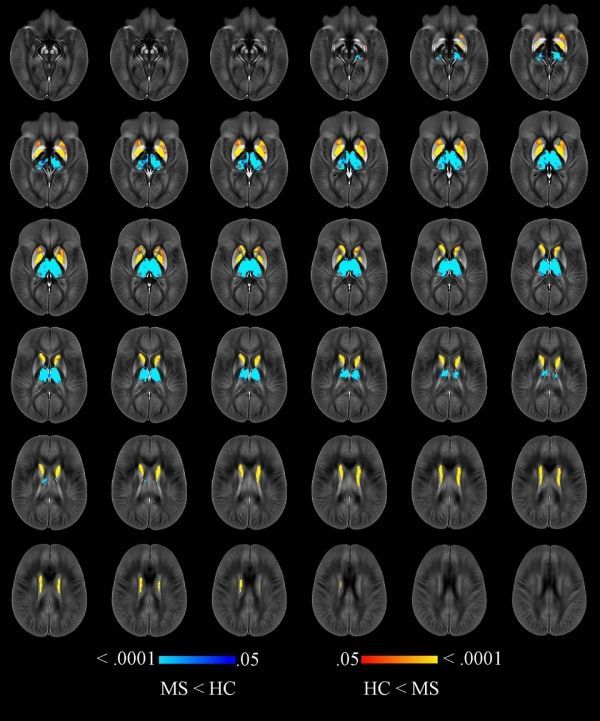

Image: Image shows voxelwise analysis of quantitative susceptibility maps within thalamus, caudate, globus pallidus, and putamen comparing all participants with multiple sclerosis (MS) to healthy control (HC) participants. Areas of higher susceptibility in participants with MS compared with HC participants are shown in red-yellow. Areas of lower susceptibility in participants with MS compared with HC participants are shown in blue-light blue. (Credit: Radiological Society of North America (RSNA))